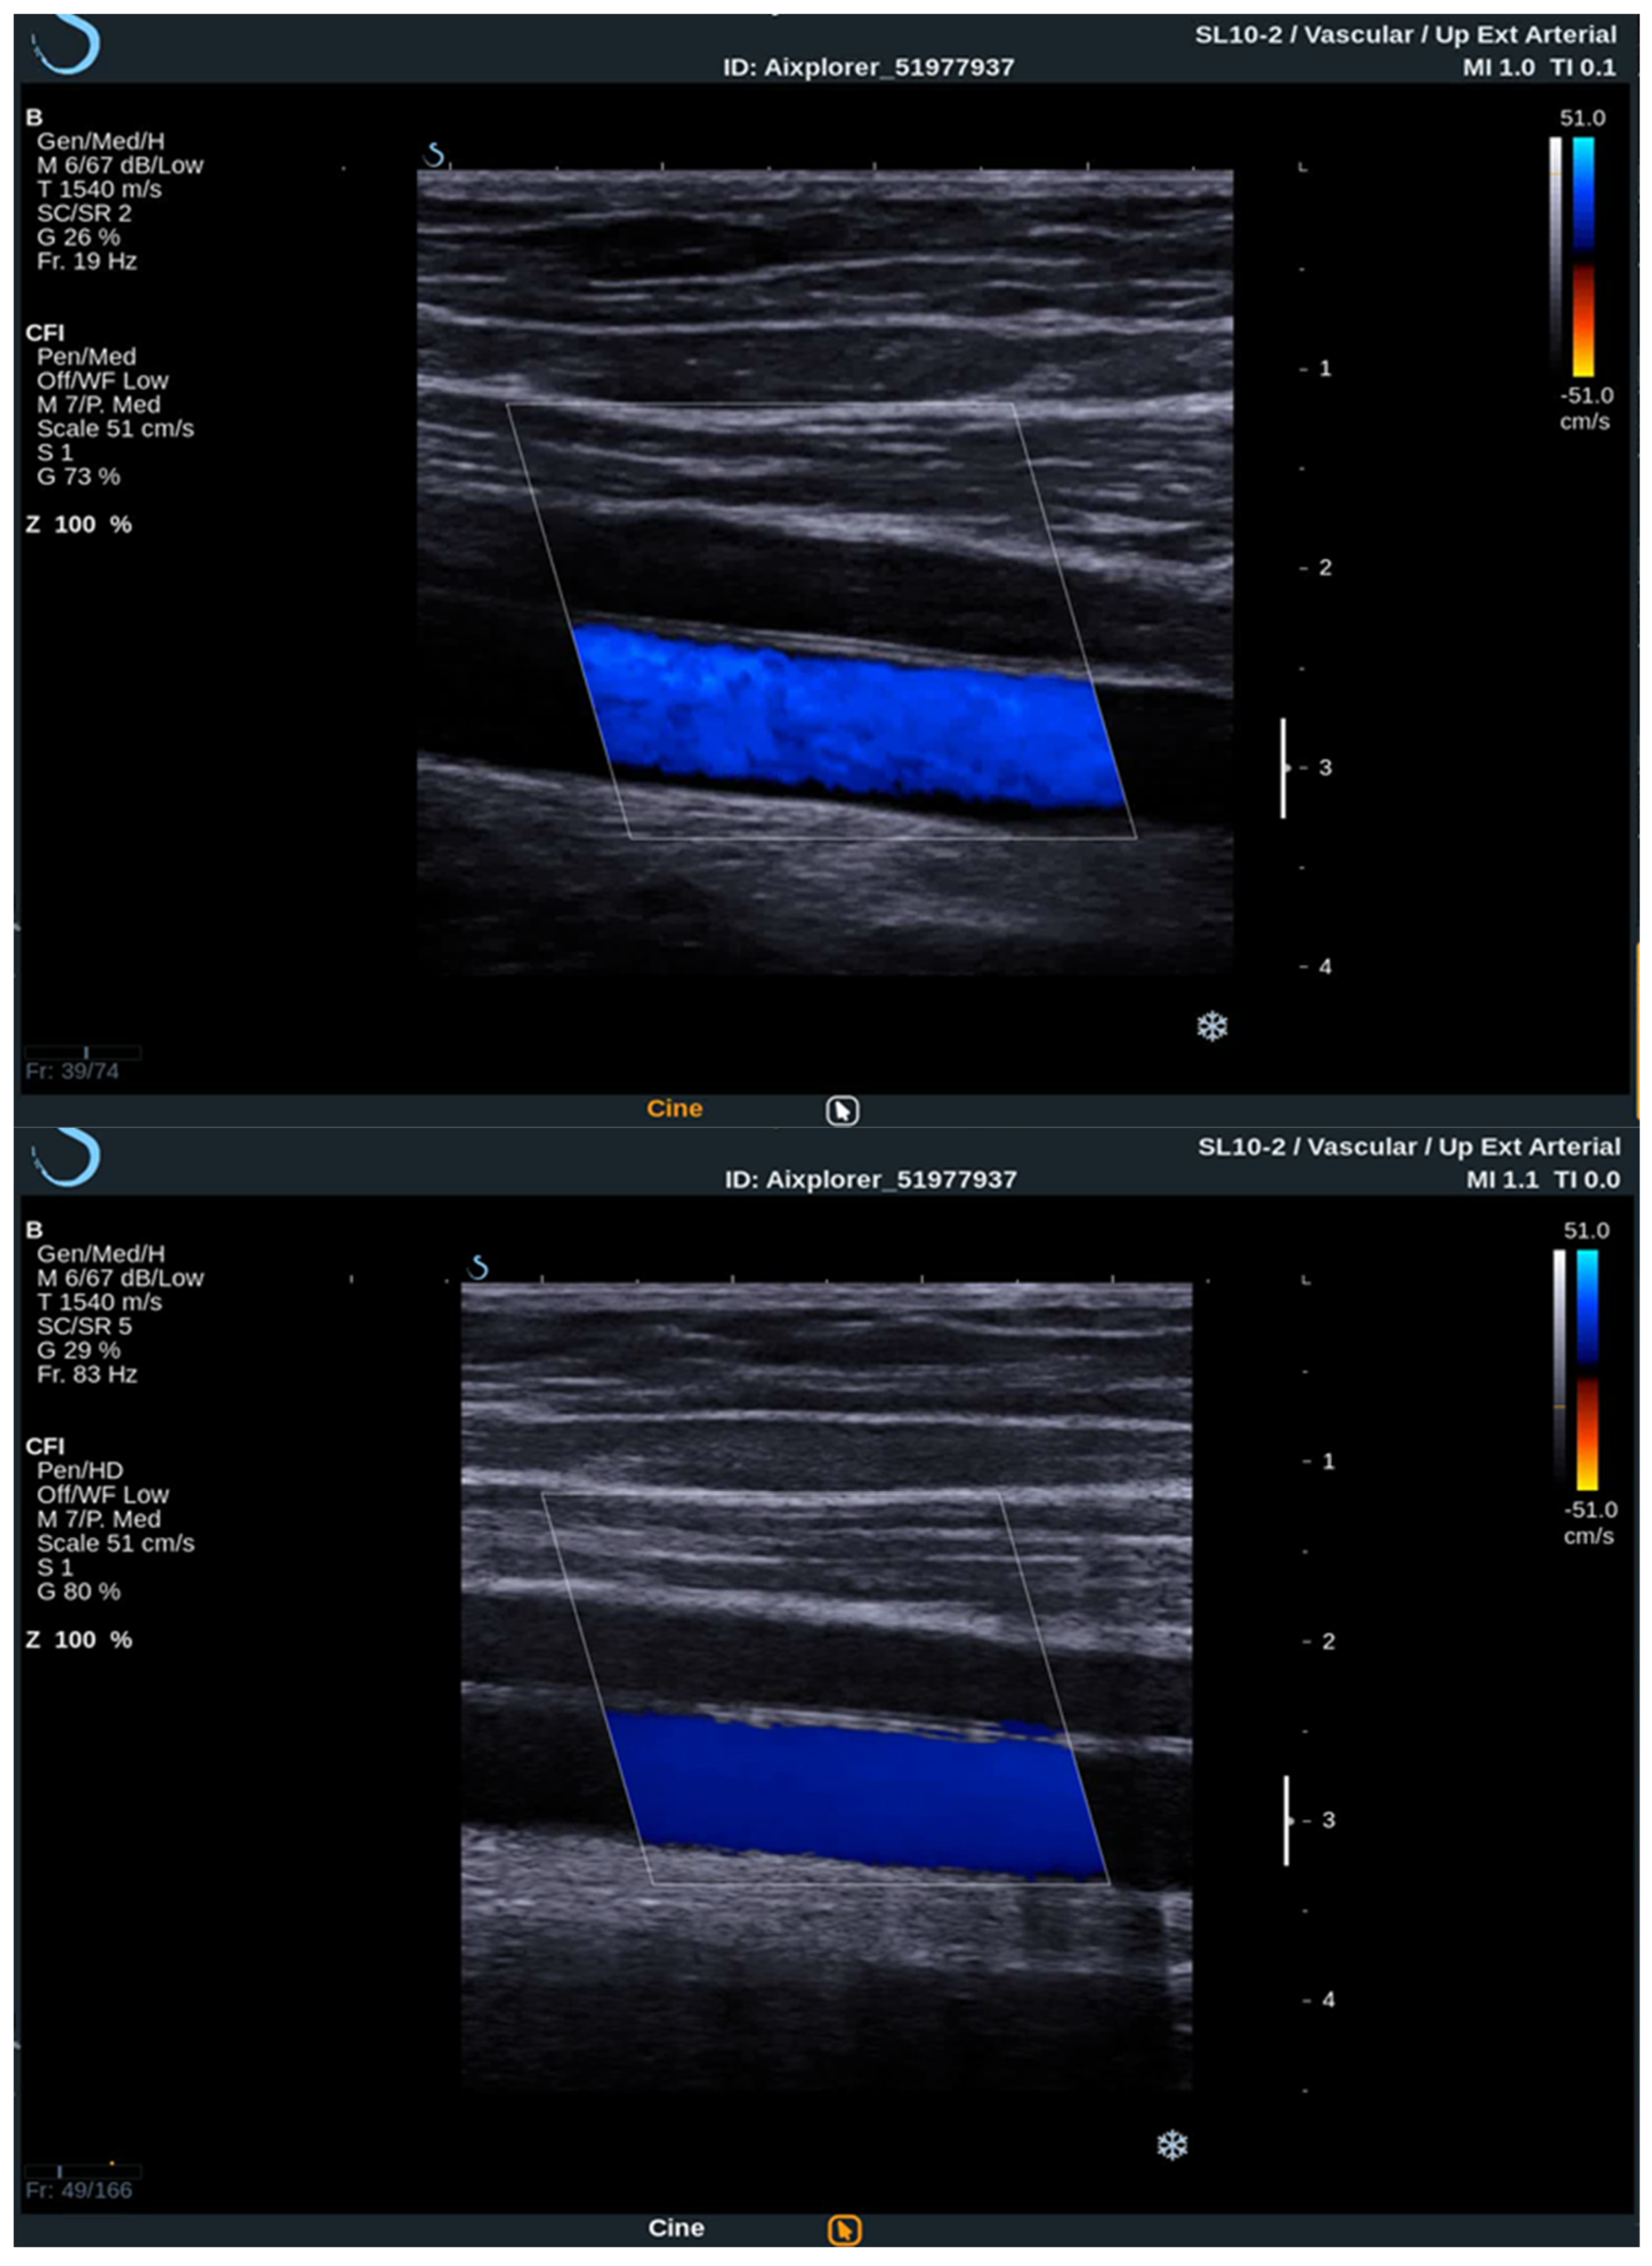

To acquire data from these modes, the practitioner switches between them analyzing the PW Doppler at the locations pinpointed by the color Doppler image. With the introduction of UltraFast™ Doppler (SuperSonic Imagine, Aix en Provence, France), quantitative data can be assessed in all pixels at the same time. Because it relies on plane waves and not focused beams in the image acquisition, there is no time lag at the sides of the image. On a conventional ultrasound device, such quantitative analysis is only possible by limiting the region of interest (ROI) to a single acoustic line. UltraFast™ Doppler allows the merging of CFI and PW Doppler mode in a single acquisition (Figure 3).

High frame rates of UltraFast™ Doppler provide a high temporal resolution on CFI, which enables the visualization of more complex, as well as fast flows. Such flow patterns can be seen in more detail, consequently enabling the examiner to establish more accurate diagnosis. To better visualize the slow flows, high frame rates are traded for higher sensitivity and better spatial resolution. This way some small vessels can only be seen using UltraFast™ Doppler and without the need for intravenous contrast agents.

Figure 3. Comparison between conventional CFI Doppler ultrasound at the top and UltraFast™ Doppler ultrasound at the bottom while examining a segment of the CCA in the longitudinal view. UltraFast™ Doppler demonstrated excellent flow sensibility and provides a framerate of more than 80 Hz.